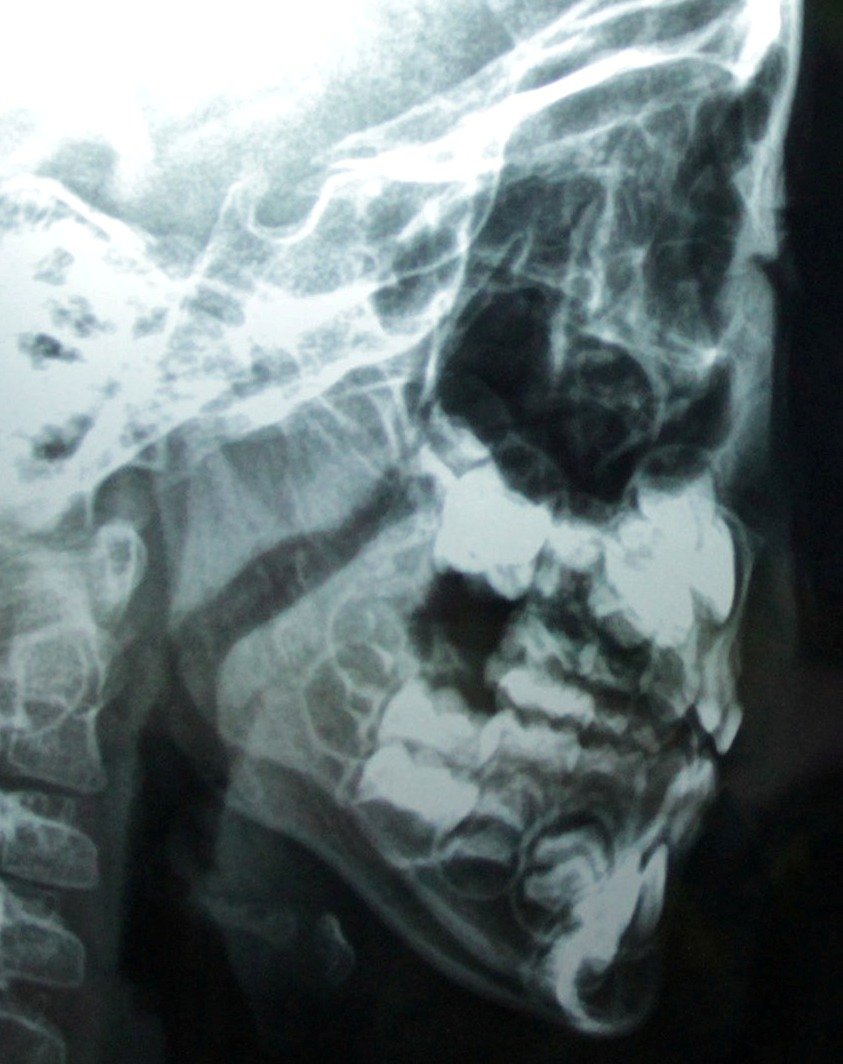

幼儿增殖腺体肥大,怎么治疗? 女孩,三岁,睡觉打鼾,习惯于张嘴呼吸,自感鼻塞,平常玩的时候偶尔鼻子也会发出”呼呼“的声音。今天做了X光,发现腺体肥大。请问我女儿的腺体肥大情况严重吗?用不用手术治疗?如果先保守治疗,用用药,会有效吗? 点击展开 匿名用户 2014-02-21 19:49 为您推荐: 其他回答 睡觉打鼾,习惯于张嘴呼吸,自感鼻塞 孩子身高体重?舌质舌苔颜色?平时手脚冷热?大小便情况?有什么样的饮食起居生活习惯?心情睡眠和运动情况? 温春梅_7INu 2014-02-22 15:30 相关问题 鼻咽部腺体肥大 诊断为宫颈腺体囊肿、宫颈肥大、慢性宫颈… 小儿8岁,经常鼻塞,流鼻涕,睡觉张嘴,打呼噜,检查增殖体肥大,需手术治疗.暑假天气热会影响手术吗?

女孩,三岁,睡觉打鼾,习惯于张嘴呼吸,自感鼻塞,平常玩的时候偶尔鼻子也会发出”呼呼“的声音。今天做了X光,发现腺体肥大。请问我女儿的腺体肥大情况严重吗?用不用手术治疗?如果先保守治疗,用用药,会有效吗?